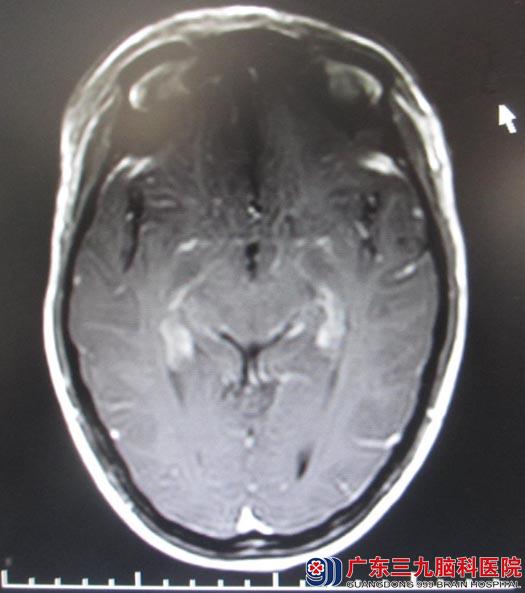

5月14日取额部冠状切口,经右额前纵裂终板入路,见鞍上肿瘤呈灰白色,边界较清,质中,血供较丰富。经视交叉前间隙及终板间隙小心分离肿瘤,肿瘤边界较清,与垂体柄粘连紧密,经小心分离后完整切除,过程中视神经、垂体柄及下丘脑等重要结构保护完整。术中出血约200ml,未输血。术后出现尿崩,高钠水电解质紊乱,垂体功能低下,经治疗后逐步控制稳定。经过术后一系列的对症处理,吴女士的病情恢复良好,视力同术前,可以下床自主活动。术后病理结果示:颅咽管瘤。

▲手术后